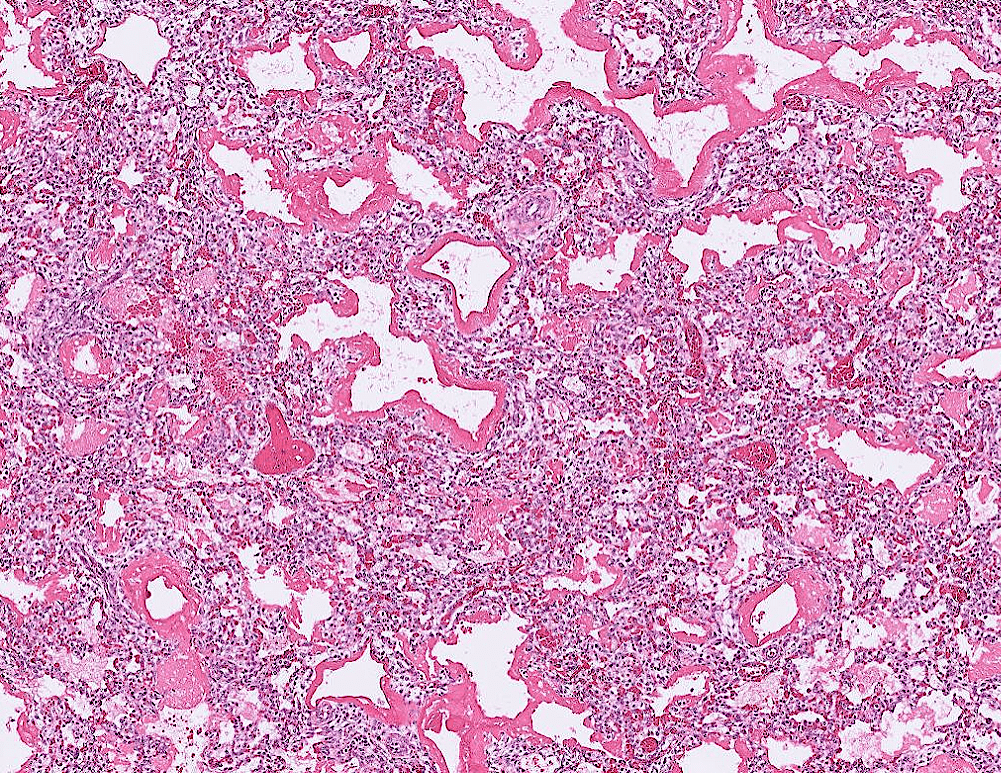

lung adenocarcinoma